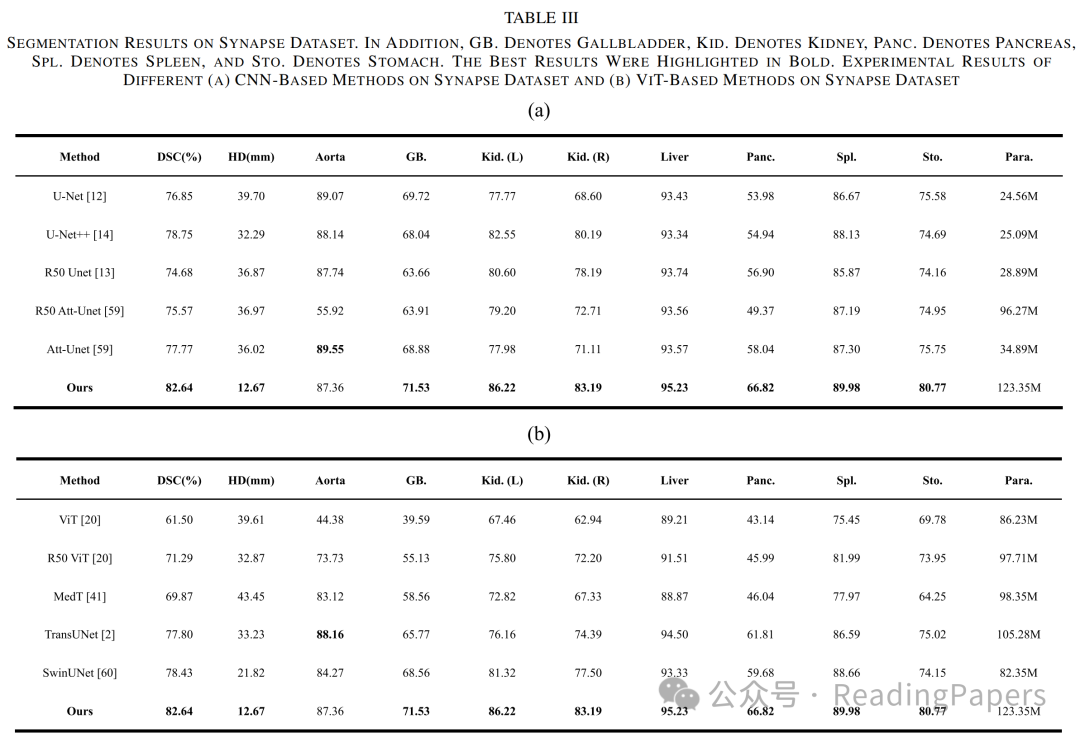

Transformer通过自注意力机制在医学图像处理中取得了显著进展,能够建模长距离语义依赖关系,但其缺乏卷积神经网络(CNN)捕捉局部空间细节的能力。本文提出了一种基于混合CNN-Transformer(MixFormer)特征提取骨干网络的新型分割网络,旨在提升医学图像分割的效果。MixFormer网络在下采样过程中无缝集成了Transformer和CNN架构的全局和局部信息。为了全面捕捉跨尺度的视角,作者引入了多尺度空间感知融合(MSAF)模块,有效实现了粗粒度与细粒度特征表示之间的交互。此外,作者还提出了混合多分支扩张注意力(MMDA)模块,用于在编码和解码阶段之间弥合语义差距,同时强调特定区域。最后,作者采用基于CNN的上采样方法来恢复低级特征,显著提高了分割精度。通过在多个主流医学图像数据集上的实验验证,MixFormer表现出卓越的性能。在Synapse数据集上,该方法达到了82.64%的平均Dice相似系数(DSC)和12.67 mm的平均Hausdorff距离(HD)。在自动心脏诊断挑战(ACDC)数据集上,DSC达到了91.01%。在国际皮肤成像协作(ISIC)2018数据集上,模型的平均交并比(mIoU)为0.841,准确率为0.958,精确率为0.910,召回率为0.934,F1得分为0.913。在Kvasir-SEG数据集上,平均Dice为0.9247,mIoU为0.8615,精确率为0.9181,召回率为0.9463。在CVC-ClinicDB数据集上,平均Dice为0.9441,mIoU为0.8922,精确率为0.9437,召回率为0.9458。这些结果表明,MixFormer在分割性能上优于大多数主流分割网络,如CNN和其他基于Transformer的结构。